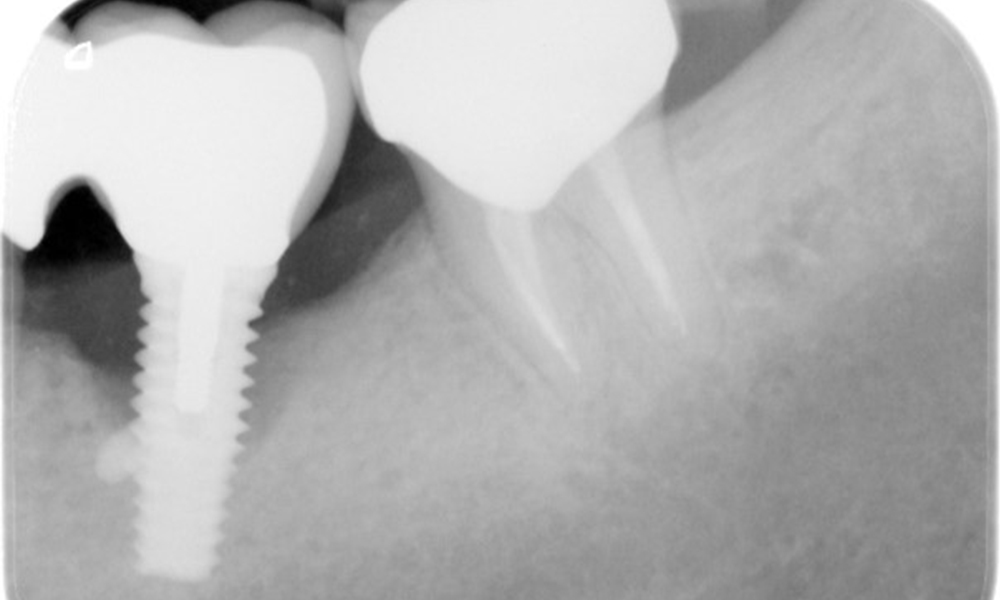

A 52-year-old patient presents at a preventive care session. The patient has no systemic disease and is not taking any medication. He has had various dental treatments and also has two active carious lesions. In addition, the patient has four implants (2nd, 3rd and 4th quadrants). He is revealed to have early periodontal disease (stage IV, grade B). His periodontal condition is stable; a probing depth of Probing depths (ST) of 5 mm is only evident at the implant in region 36. Gingivitis is also identified.

The patient has no particular risk factors with specific dental implications in his medical history. The key factor, therefore, is the requirement in terms of oral health. In this respect, there is evidence of a probing depth of 5 mm at the implant in the 3rd quadrant and, on the X-ray image, increased bone loss. The patient also has currently stable early periodontal disease and two active initial carious lesions.